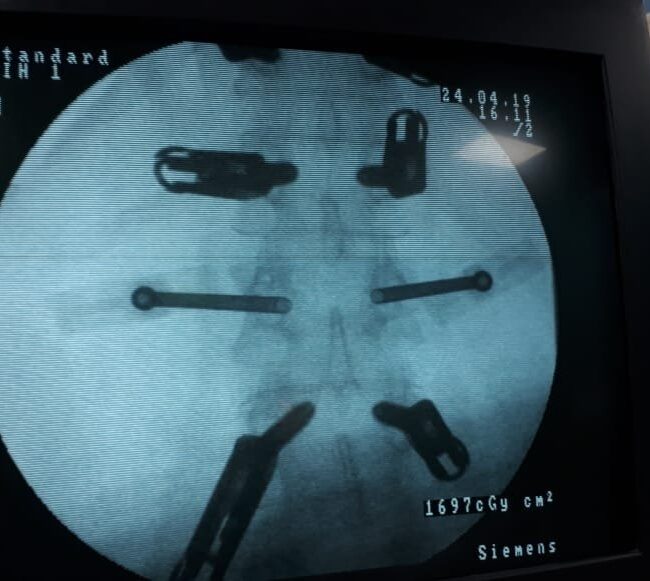

Posterior Instrumentation

Traumatic spinal injuries and spinal fusions are some spinal conditions that need instant posterior instrumentationHe places screws and MRI-compatible rods in the spine. This keeps the spine straight and stable. It prevents unwanted movement.